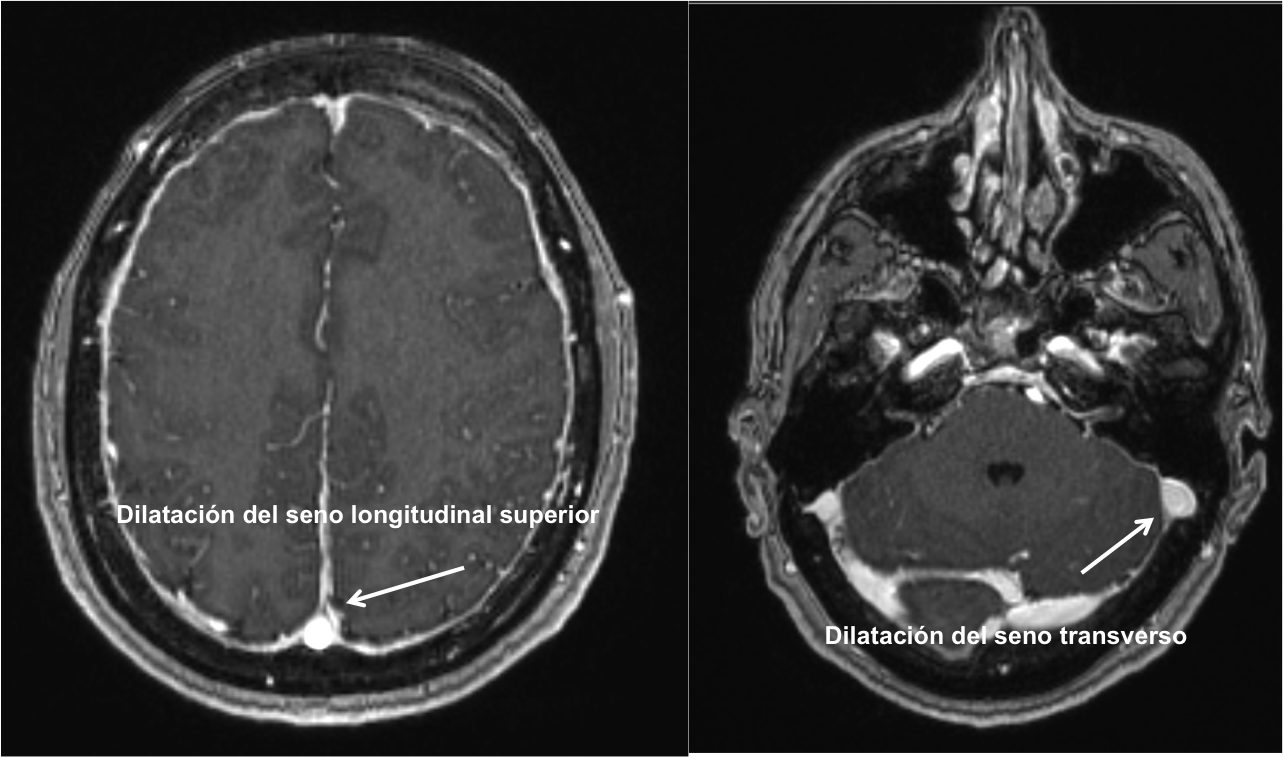

Según la hipótesis de Monro-Kellie cualquier variación del volumen de LCR debe ser compensado dado la naturaleza no compresible del cráneo. Como consecuencia, la pérdida de volumen de LCR se compensa con un aumento del volumen intracraneal y se produce una congestión venosa. Esta congestión venosa es visible en la Resonancia Cerebral y da lugar a una hipercaptación difusa meníngea.

En la Imagen 4 y 5 podemos ver el aspecto congestivo y redondeado de los senos venosos longitudinal y transverso.